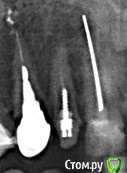

Наталия1966 Опубликовано 6 октября, 2019 Автор Поделиться Опубликовано 6 октября, 2019 (изменено) Да мне кажется, что тему закрыть можно. Топикстартер с тем же успехом может сама с собой говорить.Ну, вообщем, да, можно закрыть. Но мне было бы интересно дождаться результата установки. Все не так просто, как нам кажется с первого взгляда и случаи разные бывают. В принципе, в принципе... выдавливание гноя помогло и очень. Сегодня я проснулась и первым делом ощупка языком места - десна абсолютно ровная, потом побежала к зеркалу - гнойник ушел на его месте еще не совсем срослось и мягкий небольшой провальчик в месте гнойника, то есть заживает! Я сама еще пальцем слегка помассировала все вокруг от зуба до зуба -выдавилась еще капля гноя и все совсем опало. Десна розовая, ничего не болит. Заодно промассировала другой имплант, где мне в воспаленье вкрутил врач, он не болит, но нажим на десну и отпускание сильную пульсацию без боли вызывало. Там обмассировала и вот результат - десна лучше прилипать стала и пульсация исчезла! Вывод - никогда не надо торопиться, принимать поспешных решений. Если есть регламент - выжидать, значит нарушать его не надо 9 октября будет ровно 4 месяца. А на таком расщеплении гребня, видите, только только нормализовалось и то с вмешательством врача по десне. Нижние зубы не могут сливать сами гной как верхние, где он просто оттекал бы вниз. Тут вероятно он копиться в челюсти и не может сам исчезнуть. Вот такие пироги. Всем спасибо за внимание и добрые пожелания. Вот этим двум имплантам в июне ровно год был. Снимок в конце августа сделали. Одиночному верхнему год в ноябре будет. Изменено 6 октября, 2019 пользователем Наталия1966 Ссылка на комментарий

Наталия1966 Опубликовано 1 ноября, 2019 Автор Поделиться Опубликовано 1 ноября, 2019 (изменено) Ну, вот и все. Установлен формирователь. Снимок показал частичное обнажение импланта по передней стенке, задняя покрывает весь имплант. Доктор сказал, что в принципе это допустимо. Если не будет нагноения в передней части импланта, то считайте, что он установлен. Если будет постоянное нагноение, то два варианта - удаление самого импланта, либо попытка подсадки кости на переднюю стенку. Посмотрим, конечно. Я что думаю. Если часть импланта обнажена, то не будет ли зубной камень лепиться к этой части, тело импланта не полировано. Мож отполировать как-то. Тогда прирастет ли десна. Вообщем пока два варианта - удаленье (очень не хотелось бы) и костная пластика. 10-мм имплант утоплен по край сзади и где-то на 5-6 мм спереди. Вот такие пироги! Изменено 1 ноября, 2019 пользователем Наталия1966 Ссылка на комментарий